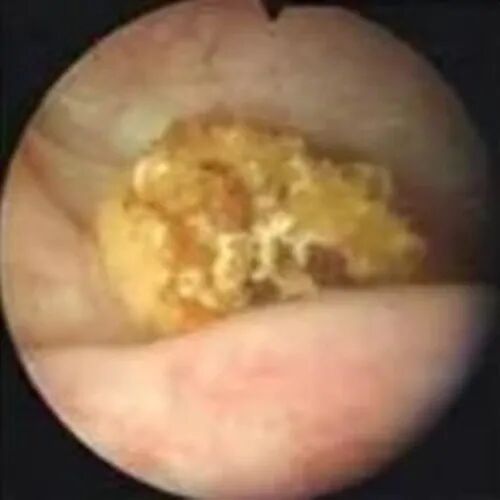

膀胱结石

膀胱镜下可发现膀胱结石,配合碎石设备,完成碎石手术。